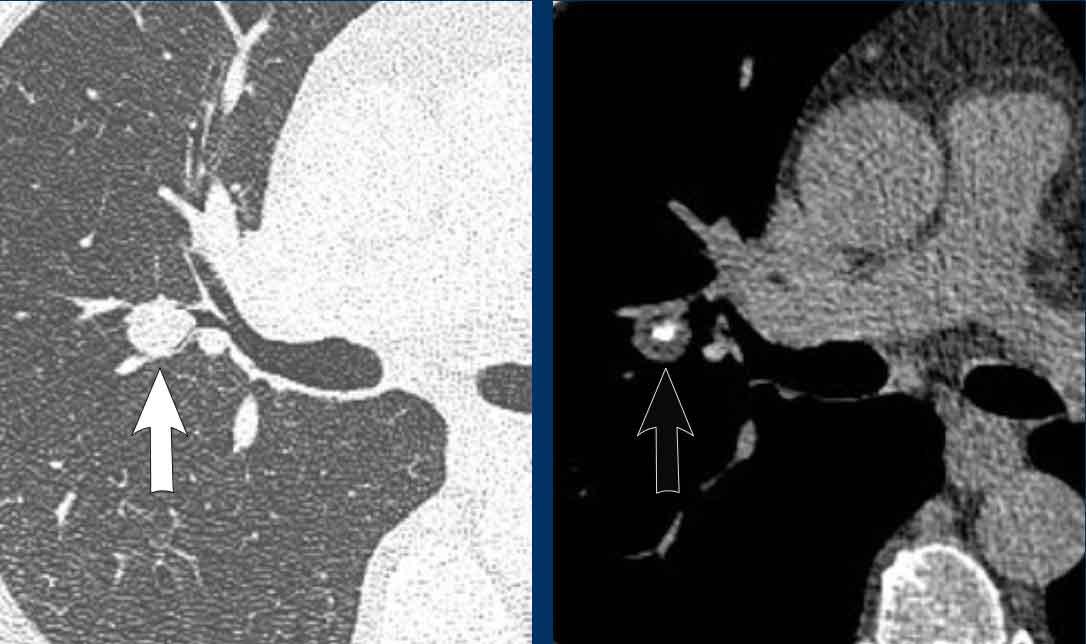

Hình ảnh

Hamartoma nội phế quản được phát hiện tình cờ ở thùy giữa phổi của bệnh nhân nam 73 tuổi.

Đặc điểm trên CT của hamartoma không phụ thuộc vào vị trí tổn thương:

- Tổn thương giảm tỷ trọng

- Tỷ trọng mỡ

- Vôi hóa dạng bỏng ngô (có thể có)

Hamartoma chứa thành phần mỡ gây tắc nghẽn phế quản thùy dưới trái ở bệnh nhân nữ 58 tuổi.